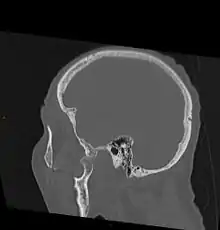

- CT image demonstrating jaw dislocation

As with other joint dislocations, clinical history and examination are important for diagnosis. Commonly, plain and panoramic X-rays are used to determine the relative position of the mandibular condyle. If a complex or unusual injury is suspected, computed tomography is most reliable in diagnosing dislocation and possibly associated fractures or soft tissue injuries.

In case of dislocations resulting from high-energy trauma, attention must also be paid to possible other injuries, particularly blunt or indirect trauma to the skull and cervical spine. Acutely life-threatening conditions need to be ruled out or treated in first line. For superior jaw dislocation in particular, serious intracranial complications such as epidural hematoma are possible and must be recognized and managed to prevent disability or even death. Therefore, neurological status has to be examined in patients with complex dislocations involving temporal bone fractures. Hearing deficits on the injured side may indicate damage to structures of the ear.[7][8]